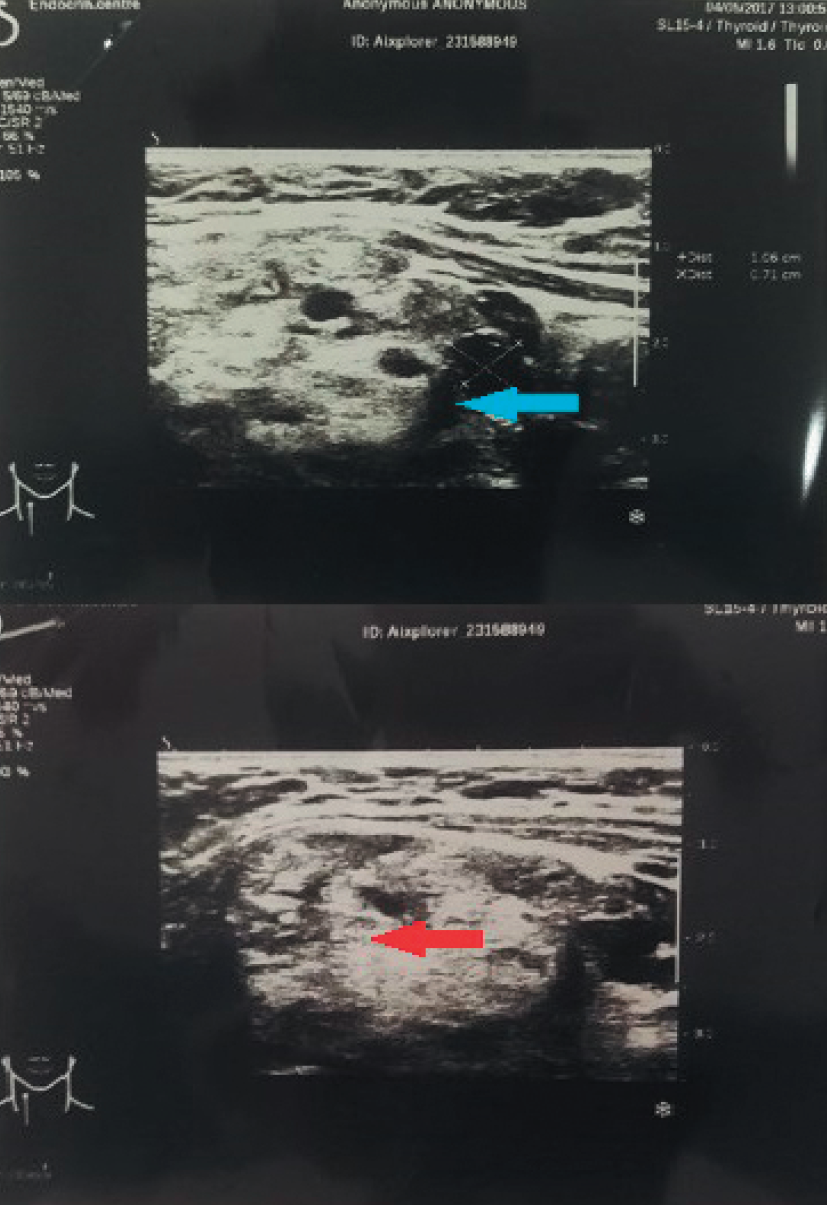

In the right lobe a conglomerate node 4 cm in diameter was defined, at the lower pole of the right lobe a hypoechoic mass of 1.4x1.0x0.7 cm was determined (echographic signs of an adenoma of the right lower parathyroid gland) (Fig. 3).

Fig. 3. Ultrasound of the thyroid gland. The blue arrow indicates a colloidal node, the red arrow - intrathyroid parathyroid adenoma.